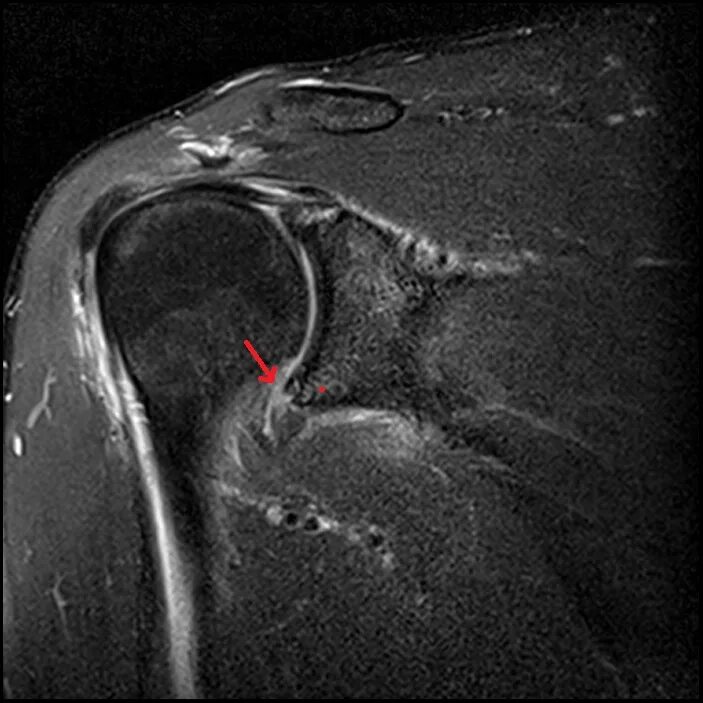

Изменение фиброзной губы гленоида